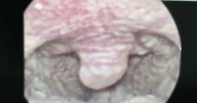

宁波市北仑区第二人民医院耳鼻喉科主任吴忠伟表示,张先生并非患普通感冒,在进行喉镜检查后,发现张先生咽喉后壁有一层白色的“雪花”,确诊为真菌性咽喉炎。导致不适的并不是细菌,而是白色念珠菌。